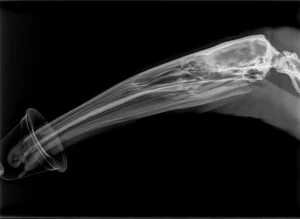

The lynx’s large broad paws are an essential adaptation that act like snowshoes, allowing the feline to tread through deep snow. The feet are covered in thick fur and can spread nearly four inches wide to quickly and easily navigate and effectively hunt in powdery snow.